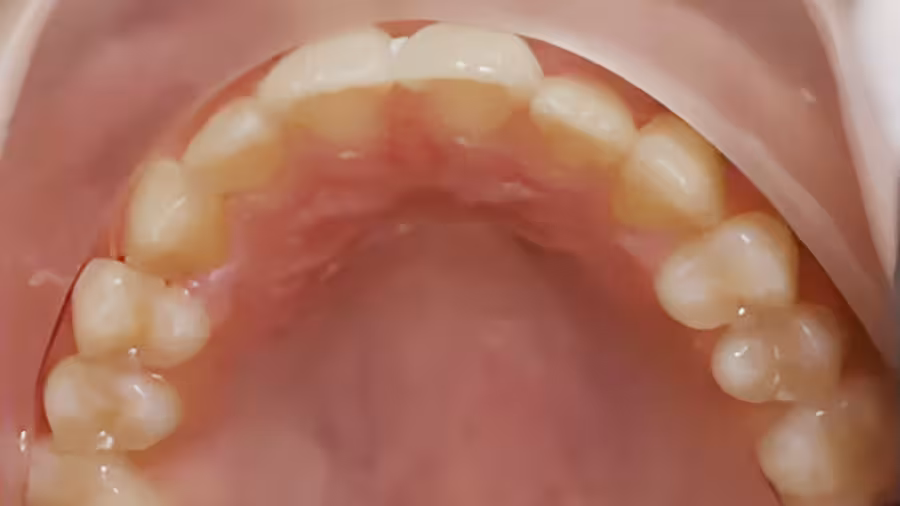

A 7 year old with severe upper and lower crowding, multiple impacted teeth. We expanded upper and lower arches and made room for all permanent teeth and impacted teeth eruption.